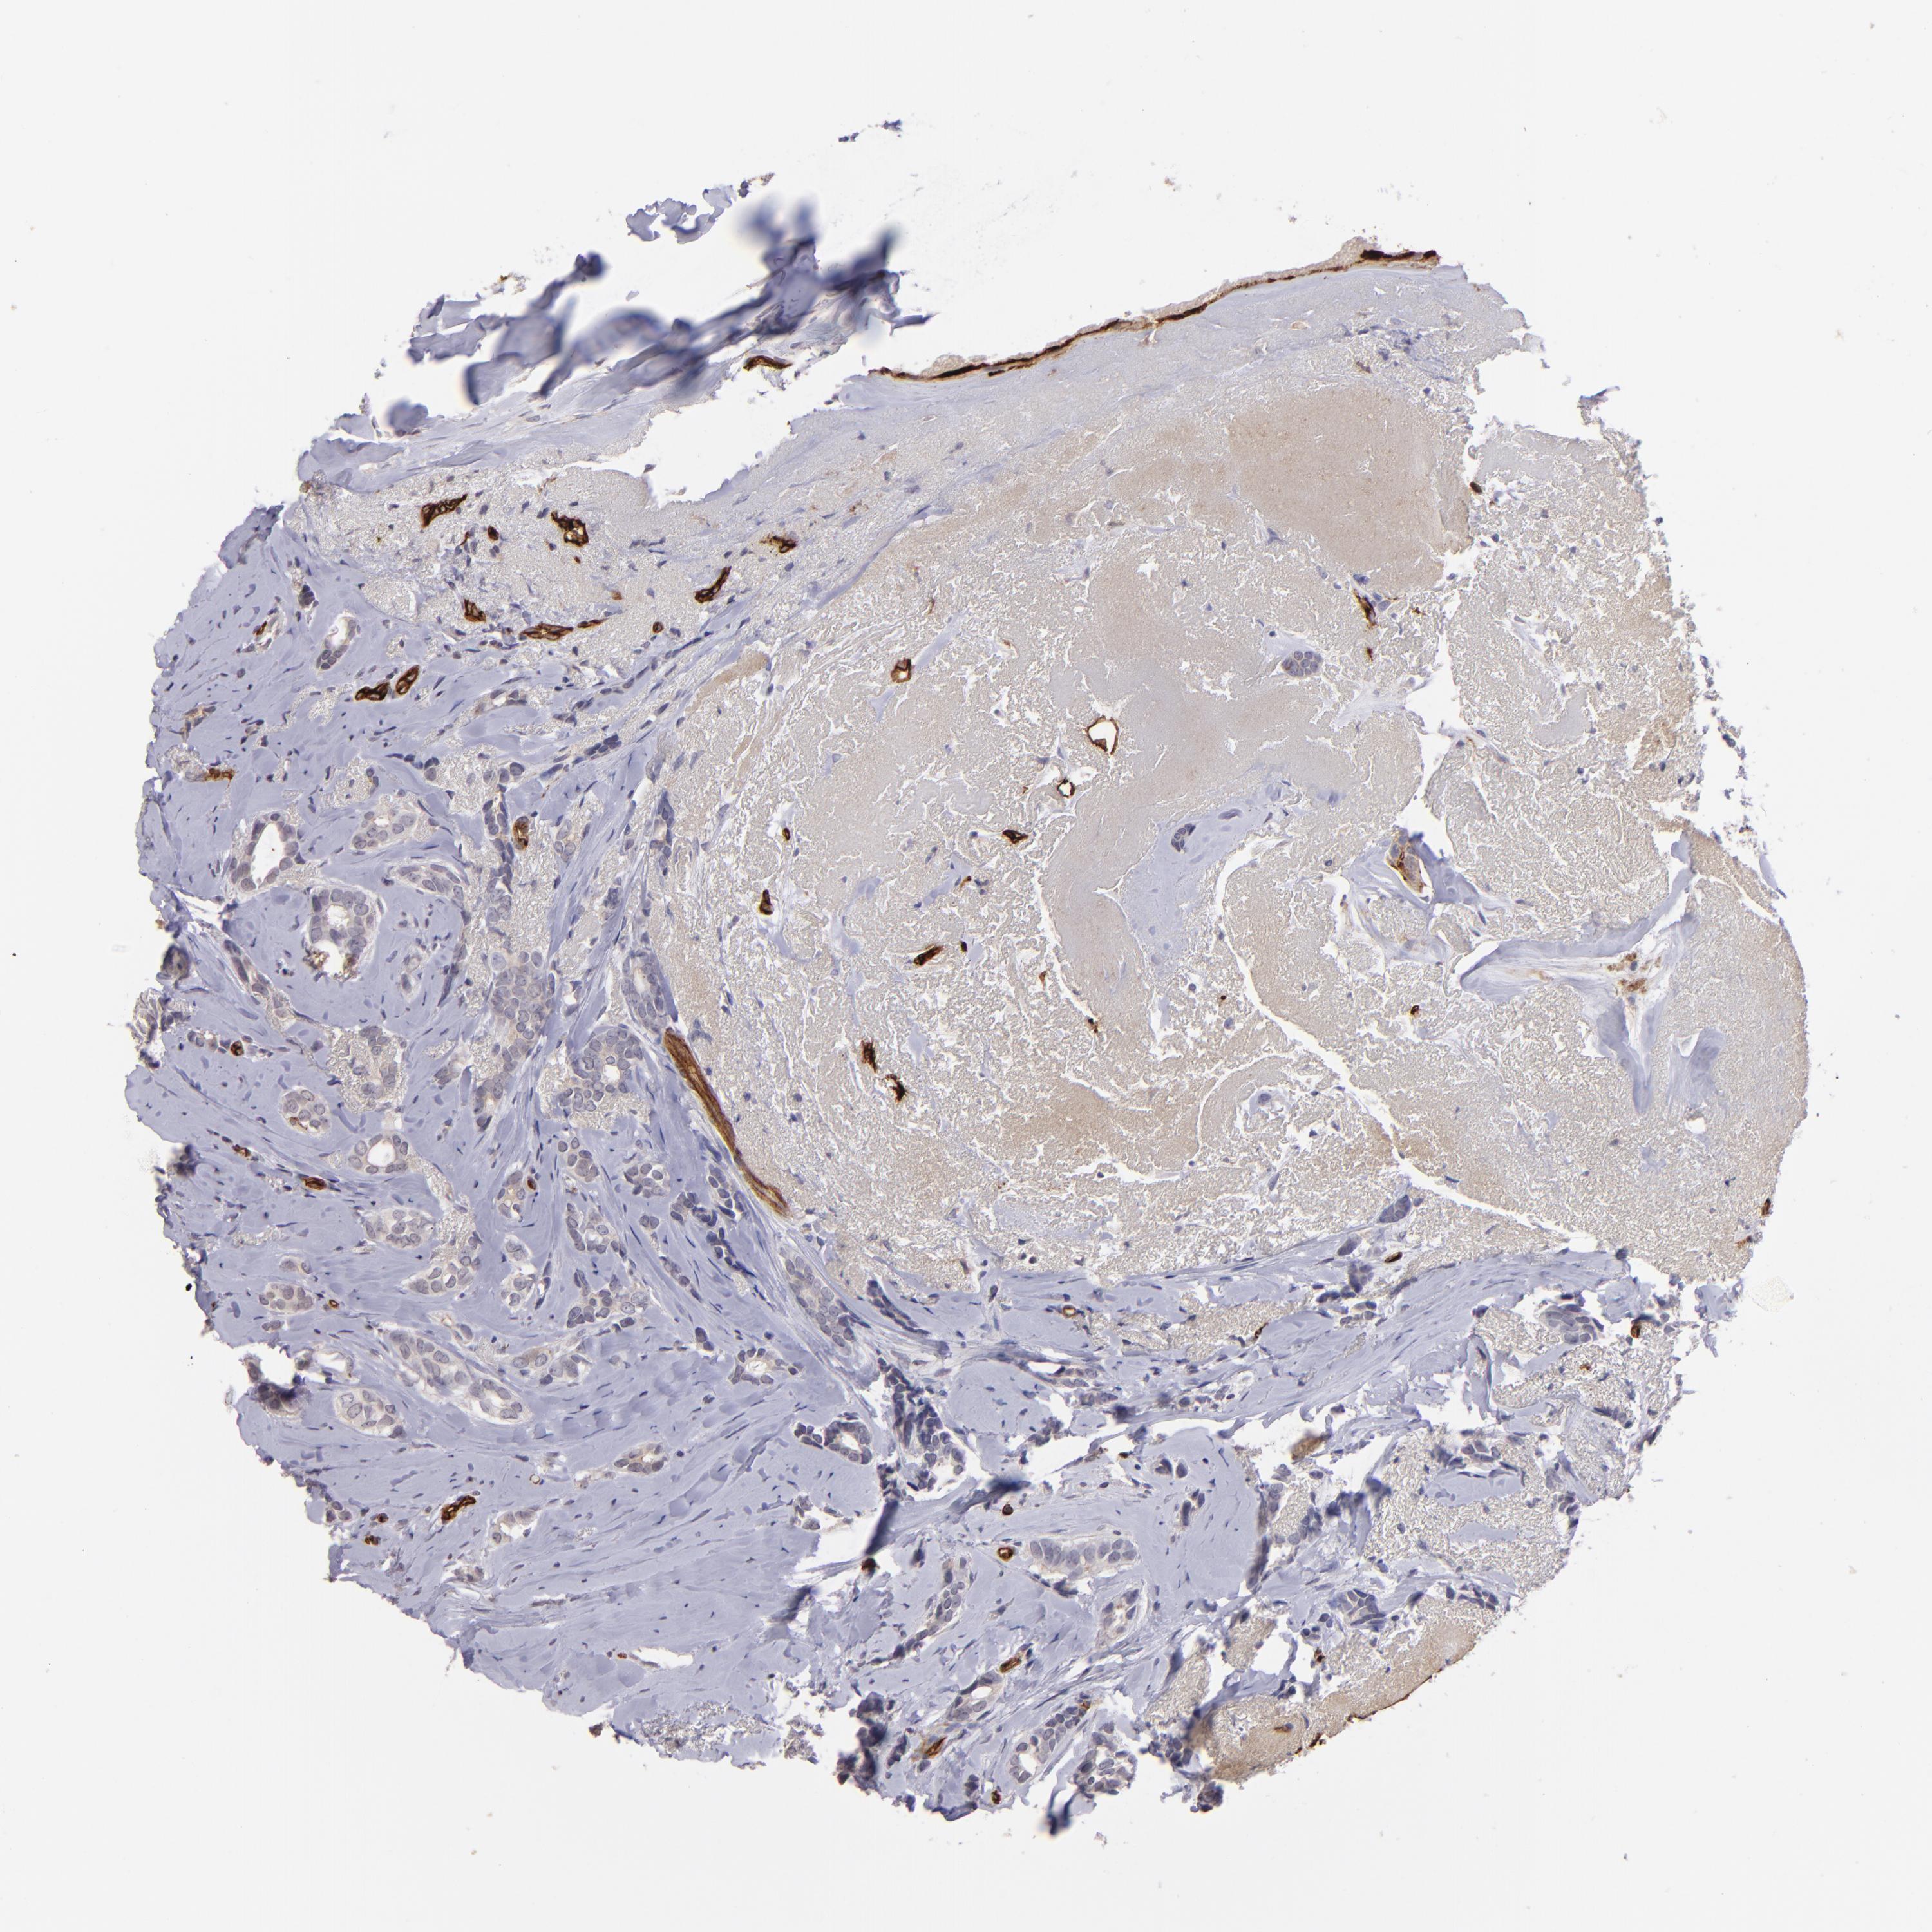

BRCA TCGA BRCA VALIDATION PROTEIN EXPRESSION

ANTIBODIES

AND

VALIDATION